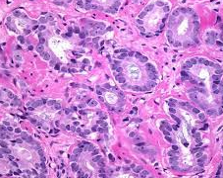

המחלקה לפתולוגיה אבחנתית בבית החולים הדסה, מחלקה מובילה בישראל ומהמובילות בעולם, מציעה שירות אבחנתי אינטגרטיבי לכל תחומי הפתולוגיה.

פתולוגיה זהו מקצוע קליני-מעבדתי המתבסס על תהליכי מעבדה מתקדמים המפוענחים על ידי רופאים מומחים הבקיאים בתחומם.